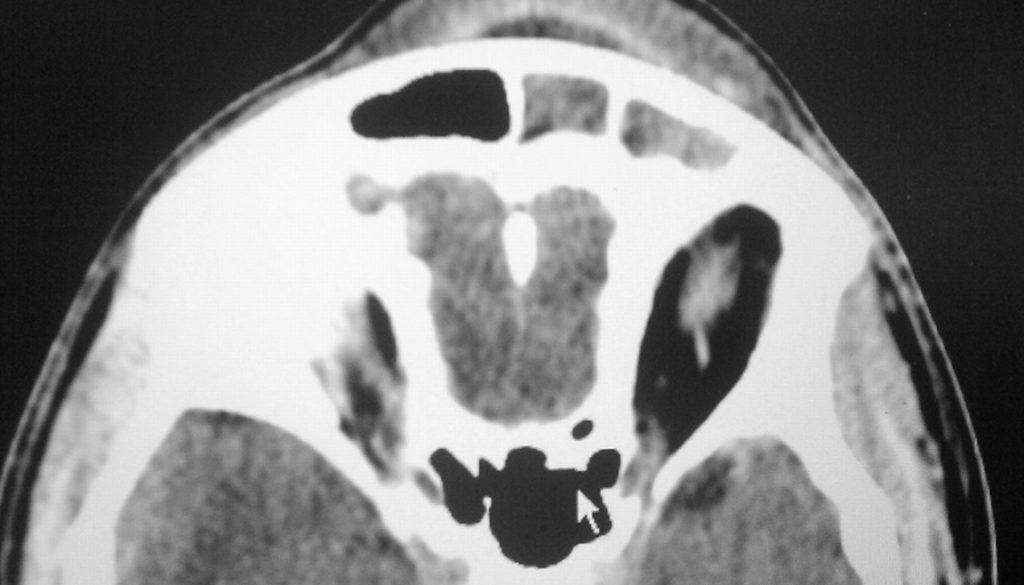

From radiopaedia.org

Pott puffy tumor and cerebral abscess Image Pott's Puffy Tumor Icd 10 citation, doi, disclosures and article data. pott puffy tumor (ppt) describes a forehead edema resulting from osteomyelitis of the frontal bone with. pott’s puffy tumor describes an infection of your frontal bone (forehead) along with an abscess that develops in the. pott puffy tumor is a subperiosteal abscess due to associated frontal skull. It is characterized. Pott's Puffy Tumor Icd 10.